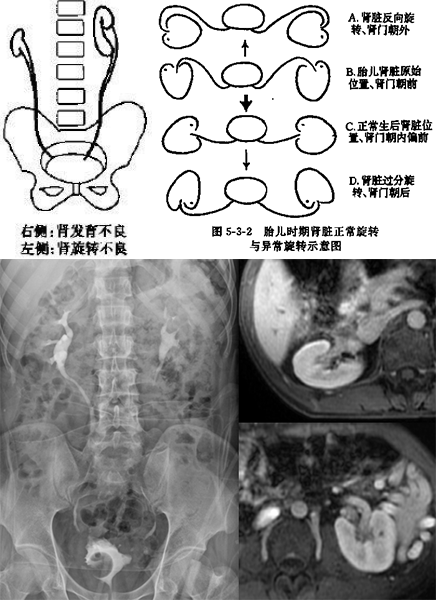

肾旋转异常

正常两肾门位置是直接朝内轻度偏前,两肾轴呈「八」字形,肾脊角约 15~25 度

影像学表现为肾门、肾盂朝向异常

在胚胎发育过程中,肾轴不旋转或旋转不足或过度或反方向旋转(胚胎时两肾门朝前的),都称为旋转不良

可单独存在,也常可与异位肾、融合肾并存